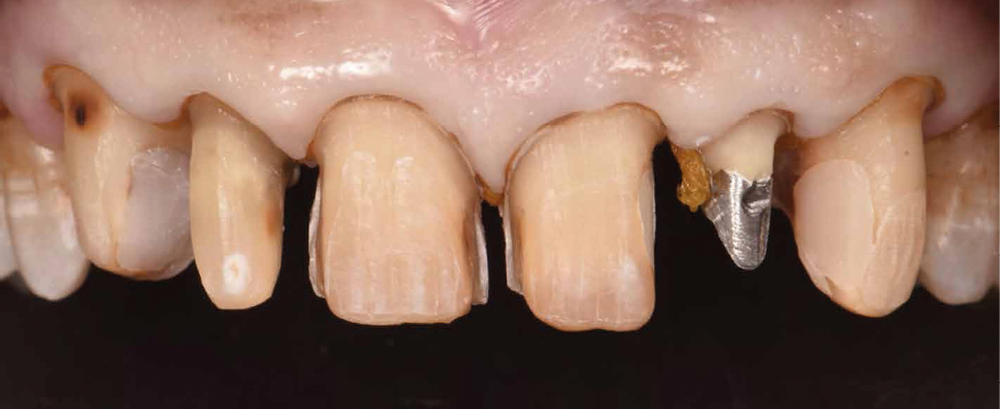

La deuxième étape comprend la préparation dentaire et la réalisation de restaurations provisoires (Voco Structur®) issues du wax-up. On traitera les lésions carieuses et les composites déjà présents seront remplacés. Les préparations sont donc guidées par ces restaurations de manière à n’avoir qu’une seule interface « céramique/dent » (fig. 3). On note donc des facettes à retour palatin, une couronne périphérique, et des couronnes ¾. La restauration corono-radiculaire sur 22 n’est pas déposée pour deux raisons : aucune lésion apicale n’est présente sur la dent et le patient est porteur d’une prothèse valvulaire aortique contre-indiquant tout retraitement endodontique (haut risque d’endocardite infectieuse).

Les restaurations provisoires sont ensuite positionnées par la technique d’isomoulage : des points de mordançages permettront la tenue de ces dernières (fig. 4).